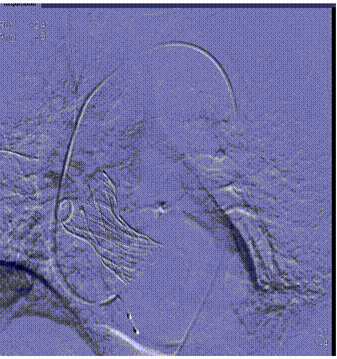

主动脉根部评估

瓣环上解剖结构评估

外周血管及主动脉弓解剖